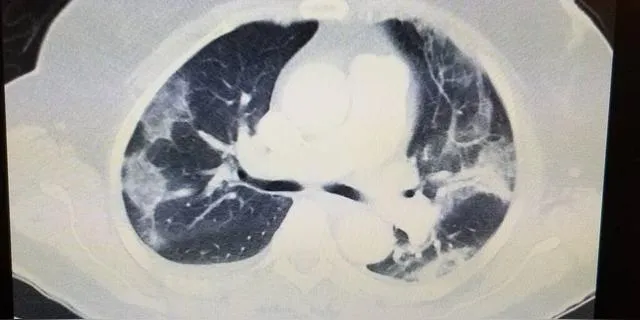

肺大泡是一种常见的肺部疾病,它不仅影响患者的呼吸功能,还可能引发严重的并发症。了解肺大泡的成因、症状和治疗方法,对于有效管理和预防这种疾病至关重要。

肺大泡,顾名思义,是指肺部出现的异常膨胀的气泡。它通常由小支气管的活瓣性阻塞引起,导致肺泡内气体积聚,最终形成大泡。肺大泡可以是先天性的,也可能后天形成,常见于慢性支气管炎和肺气肿患者。

小的肺大泡往往没有明显症状,但随着肺大泡的增大,患者可能会感到胸闷、气短。更严重的是,肺大泡突然增大破裂可能导致自发性气胸,引起严重呼吸困难和类似心绞痛的胸痛。